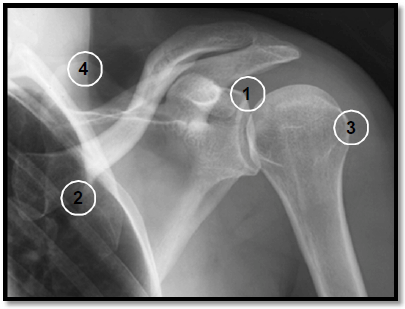

A numeração da imagem radiográfica representa, em ordem crescente, as seguintes estruturas anatômicas: